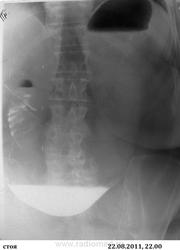

Интересный случай. Высокая тонкокишечная непроходимость. Желчный камень.

Случай любезно предоставлен моим коллегой. Пациентка 67 лет, очень полная, поступила ургентно с подозрением на о.панкреатит.

Анализы в норме. Из анамнеза ничего существенного. Жалобы: боли в эпигастрии, рвота съеденной пищей. Рентгеноскопия не работает. По УЗИ диф.изменения п.ж. Дан барий с последующим пассажем. Рвота барием на 2-3-4 сутки от поступления. Ваше мнение?

Я так понимаю, что барий еще в  растянутом желудке и частично в тонкой кишке?Или я чего-то не понимаю ,но   похоже на   механическую непроходимость.

Декомпенсированый блок дистальнее нисходящей части 12 кишки. Причина - может быть любой, но если есть соответствующая клиника - вполне может быть обусловлен острым панкреатитом.

Конкремент из желчного пузыря - пролежень - в 12 п. кишку и ее закупорка - непроходимость. Газ в протоках печени.

Так точно!laugh Камень из нижнего колена 12-перстной кишки протолкнули за трейцерову связку и удалили.

Спасибо! А ведь уже на обзорном - виден газ в протоках печени...